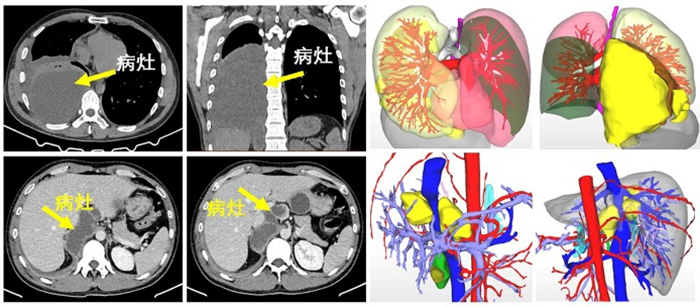

這是一名年輕男性患者,因“右上腹及肩背部疼痛5天”來到肝膽胰外科就診。經(jīng)胸部增強(qiáng)CT檢查提示右胸腔后側(cè)、下縱膈氣管旁囊性占位性病變,右肺下葉壓縮性肺不張。腹部增強(qiáng)CT提示肝包蟲病,腹膜后多發(fā)囊性占位病變,考慮為包蟲病。

肝膽胰外科楊闖主任認(rèn)為患者為藏區(qū)群眾,有疫區(qū)接觸史,結(jié)合影像學(xué)資料,肝棘球蚴病、腹腔棘球蚴病、胸腔棘球蚴病明確,需要手術(shù)治療。因病灶涉及多系統(tǒng)器官,手術(shù)較復(fù)雜,需要多學(xué)科協(xié)作完成,在醫(yī)院醫(yī)務(wù)部羅亦剛主任的主持下,楊闖副院長邀請郭中恒院長、麻醉科曾浩主任等科室負(fù)責(zé)人開展MDT(多學(xué)科會(huì)診)討論。

通過討論一致認(rèn)為,從多維度考量,胸、腹部病灶同期手術(shù)切除的方案是可行的,取得患者家屬同意后,決定為患者實(shí)施胸腹腔病損切除、右肺部分切除、肝部分切除等手術(shù)。

經(jīng)充分術(shù)前準(zhǔn)備,趙科醫(yī)生擔(dān)任主麻,曾浩主任為麻醉指導(dǎo),郭中恒主任醫(yī)師主刀為患者實(shí)施右側(cè)胸部病損切除、部分肺切除術(shù),接著由楊闖主任醫(yī)師為患者實(shí)施肝部分切除聯(lián)合腹膜后包蟲切除術(shù),歷經(jīng)近9小時(shí)奮戰(zhàn),手術(shù)順利完成。